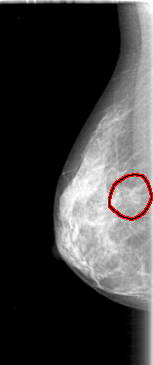

D_4085_1.RIGHT_MLO

RIGHT_MLO LINES 5101 PIXELS_PER_LINE 2131 BITS_PER_PIXEL 12 RESOLUTION 43.5 OVERLAY

FILE: D_4085_1.RIGHT_MLO.OVERLAY

TOTAL_ABNORMALITIES 1

ABNORMALITY 1

LESION_TYPE MASS SHAPE OVAL MARGINS OBSCURED

ASSESSMENT 0

SUBTLETY 3

PATHOLOGY BENIGN

TOTAL_OUTLINES 1

BOUNDARY